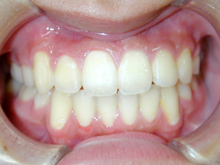

口元の過度な緊張はなくなり、余裕ができました。側貌は著明な改善が認められます。

![]() |

![]() ![]() |

矯正の場合は副作用として治療中のむし歯の発生や歯周病の悪化の危険性以外にも、

歯根吸収、歯根破折、歯髄変性、歯髄壊死などの可能性があり、注意が必要です。